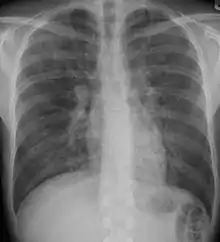

Pneumocystis pneumonia can present with interstitial lung disease, as seen in the reticular markings on this AP chest x-ray.

A chest X-ray demonstrating pulmonary fibrosis due to amiodarone

Chest radiography is usually the first test to detect interstitial lung diseases, but the chest radiograph can be normal in up to 10% of patients, especially early in the disease process.[13][14]